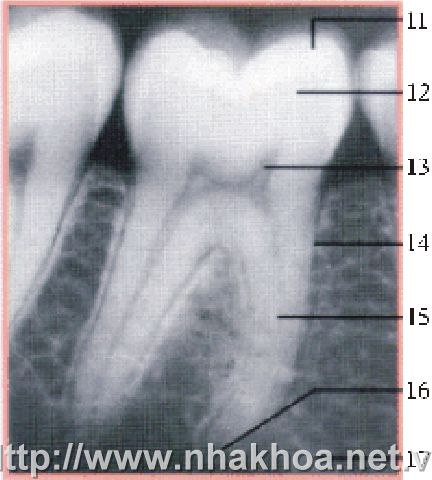

Hình ảnh X-quang một răng hàm điển hình

(11) vùng men răng, (12) vùng ngà răng, (13) vùng tuỷ thân răng, (14) vùng dây chằng quanh răng

(15) vùng tuỷ chân răng, (16) vùng lỗ chóp tuỷ răng.